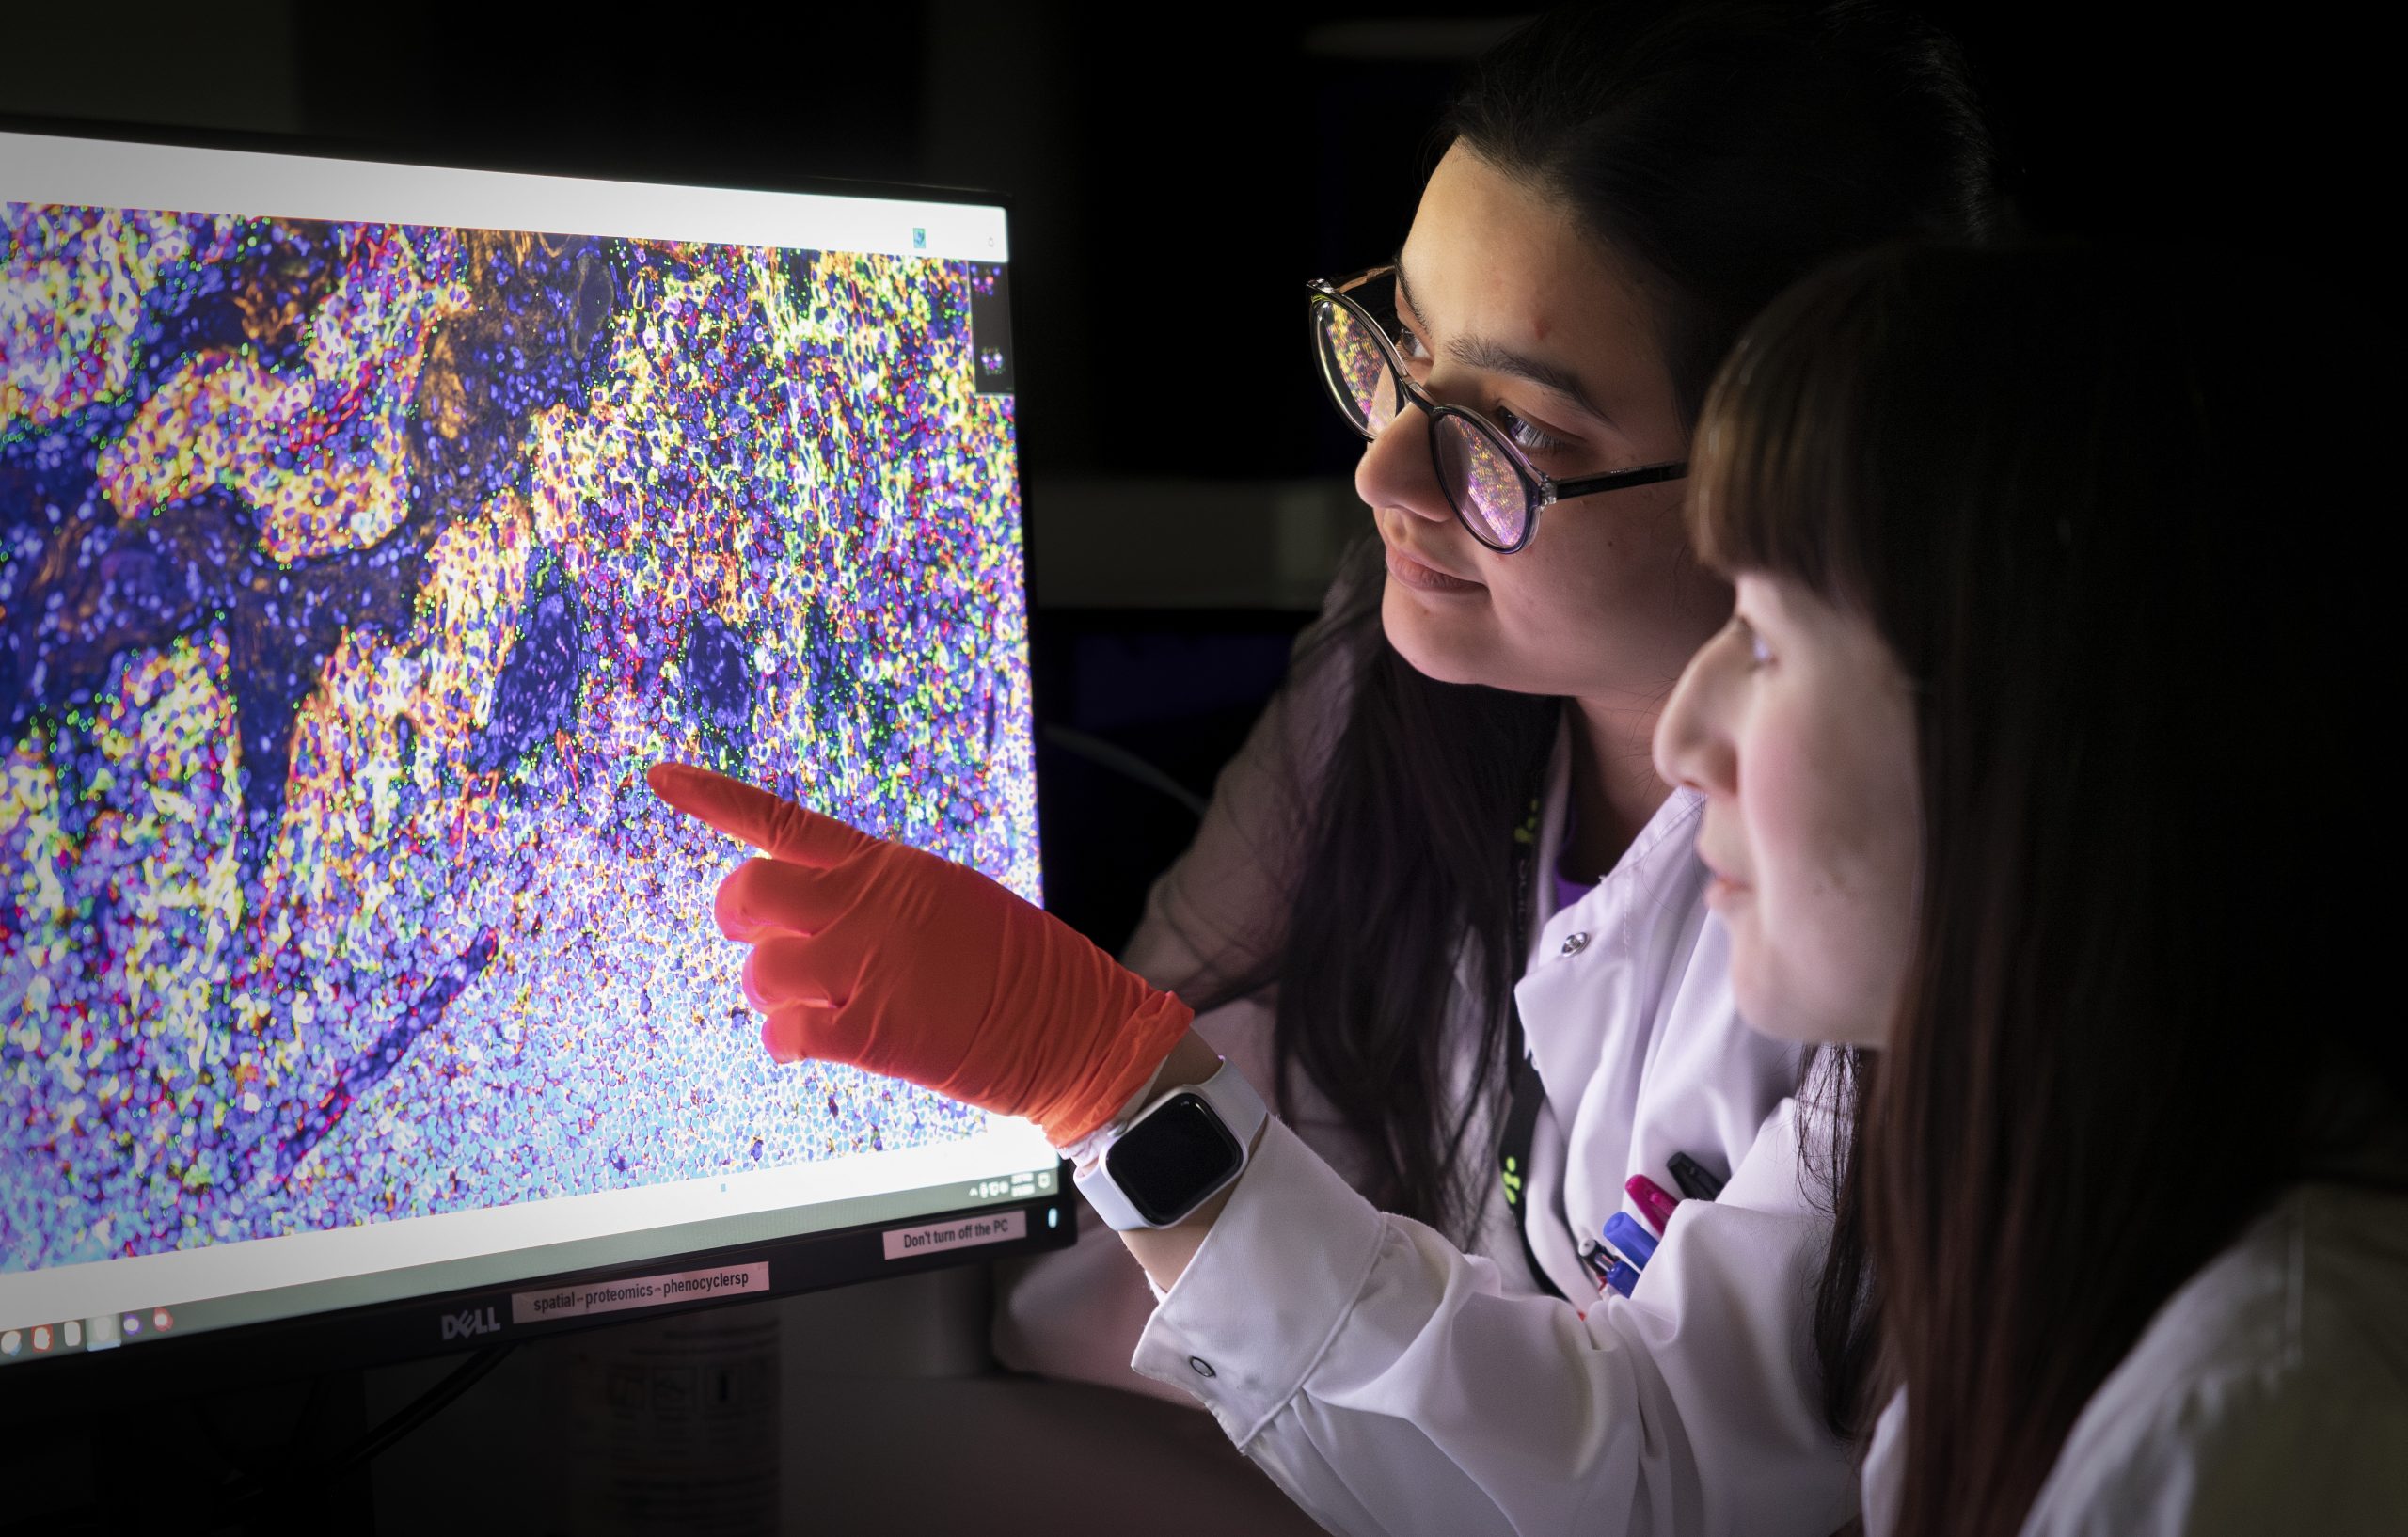

Spatial Proteomics

The aim of the Spatial Proteomics unit is to do full-service multiplexed immunofluorescence (IF) projects covering discovery, translational and diagnostic research questions. The feasibility of proposed projects is assessed, then we perform everything from project design, sample preparation and imaging to give you the best results possible. Initial analysis suport can be given. Our instrumentation and methods allow us to run targeted spatial proteomics analysis of up to 50 markers at single cell level in tissue sections (fresh frozen or FFPE) in human or mouse sections. In the Spatial Proteomics unit, we offer:

In the Spatial Proteomics unit, we offer:

- High-plex IF with Phenocycler-Fusion (Akoya)

- Medium-plex IF with COMET (Lunaphore)

- Low-plex IF with Signal Star (Cell Signaling Technology)

- Image scanning and spectral unmixing for up to 8 colors

- Antibody conjugations for our IF applications

- HE stainings in combinations with IF

Explore more